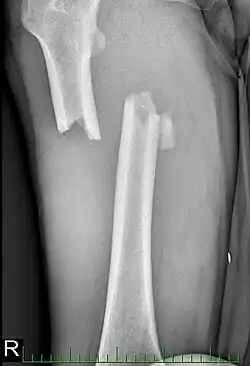

| Fratura da diáfise do fêmur com deslocamento e fragmentos. | |

Para fraturas da diáfise, a redução e haste intramedular são recomendados atualmente. O osso é realinhado, e em seguida uma haste de metal é fixada atravessando a medula óssea. A haste é estabilizada com pregos em cada extremidade. Este método oferece menos exposição, 98% de consolidação, menores taxas de infecção (1%-2%) e menos cicatrizes.[13]